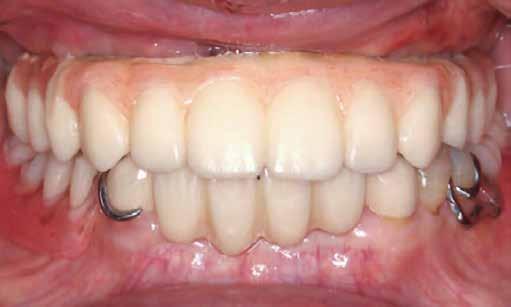

DIGITÁLISAN KÉSZÍTETT TELJES FOGPÓTLÁS

Esetbemutatás

Az alábbi eset ismerteti a Grammetry innovatív csavartechnológiával kombinált felhasználásának a jellemzőit és az előnyeit. Egy 63 éves férfi beteg jelentkezett rendelőnkben, negatív kórtörténettel, mindkét állcsontját érintő, hiányos fogazattal. Diagnosztikai adatgyűjtést végeztünk, beleértve a teljes száj digitális röntgenfelvételeit (RVG 6200, Carestream Dental; 11. a ábra), az intraorális felvételeket (Medit i700 wireless; 11. b-c ábra), a nagy látómezejű CBCT-vizsgálatot (Carestream

9600; 11. d ábra), valamint az intra- és extraorális fotókat (11. e ábra). Az alsó állcsontban egy retineált szemfogat, valamint számos mobilis és fájdalmas fogat detektáltunk.

A felső állcsonton hasonló állapotot regisztráltunk: romló, fájdalmas, mobilis fogak és kiterjedt carieses léziók. Habár a mandibulán szignifikáns csontveszteséget tapasztaltunk, az okkluzális magasság (VDO, vertical dimension of occlusion) lehetővé tette az FP-1 típusú protézis elkészítését mindkét állcsont esetében.

Az adatok értékelése alapján több kezelési tervet is kidolgoztunk és prezentáltunk a páciens számára. A mérlegelt kezelési koncepciók között szerepelt a kivehető fogpótlások megtámasztásához elég stabilnak megítélt fogak megmentése; az implantáció rögzített és kivehető protézisek kombinációjával; az implantátumokon elhorgonyzott overdenture protézisek; és a teljes szájimplantátumokkal történő rehabilitációja. A különböző kezelési javaslatok áttekintése után a páciens a legutóbbi lehetőséget választotta.

A regisztrált adatokat, valamint az előzetes terveket az implantálandó területekről (Blue Sky Plan, Blue Sky Bio) elküldtük a fogtechnikának (ROE Dental Laboratory) áttekintésre. A CBCT-vizsgálatból származó 3D-s adatokat ezután összevontuk az IOS-adatsorral, az esetek restaurációs célú megoldásának meghatározására. A fogtechnika ezután CAD-szoftver segítségével megtervezte az ideiglenes, teljes, csavarral rögzített fogpótlásokat, a protézisekhez szükséges, tervezett VDO-értékek mellett. A 3D-ben rekonstruált csontvolumen segítségével vizualizált fogpozíció által könnyebb volt meghatározni a legkedvezőbb helyeket az implantátumok beültetésére. A fogtechnikával virtuális, távoli tervezést végeztünk a teljes sablonos, irányított műtéti terv véglegesítése céljából (CHROME GuidedSMILE, ROE Dental Laboratory), amely a VDO 2 mm-es növelését is magában foglalta. Az esetet elküldtük gyártásra. A CHROME GuidedSMILE protokoll több komponensből áll, amelyek kombinálható megoldásokat nyújtanak: fémvázat a csontredukció ellenőrzésére, az oszteotómiák előkészítésére, teljes sablonokat az implantátumok behelyezésére, az implantátum mélységének, útjának és rotációs indexelésének ellenőrzésére, a Multi-unit fejek pozicionálására és az ideiglenes restaurációk átadására [1].

A műtétet mindkét állcsonton egy ülés alatt végeztük el intravénás szedációban. Az összes meglévő fogat eltávolítottuk, majd a kiválasztott fogakat a Smart Dentin Grinder (KometaBio) segítségével porítottuk és sterilizáltuk, hogy autograft csontpótlóként használhassuk fel [2] (12. ábra) Biológiai fúrórendszert alkalmaztunk az anatómiai alveoláris csont alakításához (Universal Shapers), (13. ábra). Az alveoláris csonthoz gyémántfúrókat alkalmaztunk mind az implantátumok, mind a hézagfogak területének esetében. Ennek célja az volt, hogy a kezdeti adatgyűjtés alapján megállapított fogméreteknek megfelelően, fokozott esztétikát